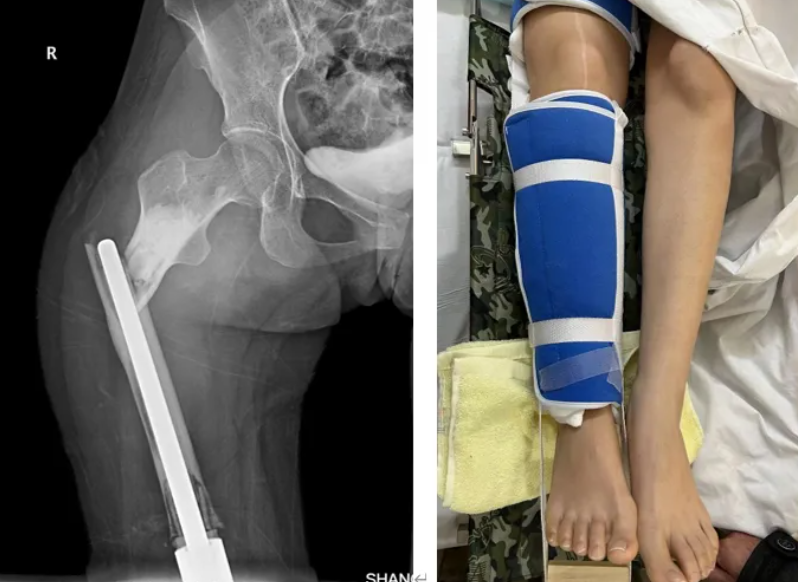

天有不测风云,在术后第七年患者因外伤导致右大腿畸形肿胀,活动障碍。遂至当地医院就诊摄片发现假体周围骨折。立即转运至我院,急诊给予手法复位+下肢牵引。

图示:假体周围骨折,急诊予以右下肢牵引